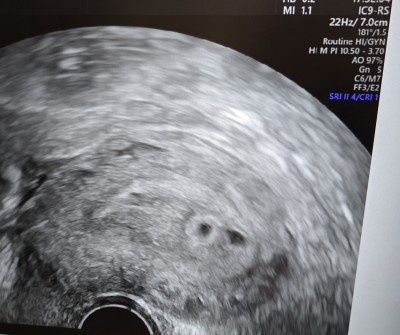

Merhaba , bugün çok sancılandığım için hastaneye gidip muayene oldum ve ilk ultrasondu. Kendi kadın doktorumda 7 +2 de randevu almıştım herşeyi netleşir o zamana kadar diye. Hastanede ki doktor önce bir kese gördü ölçtü haftasıyla uyumlu dedi . Sonra ikinci keseyi gösterdi burda da bir tane var ama boş dedi.Küçük keseyi yaklaştırdığında  bebeği gördüm doktora da söyledim henüz erken biri boş gelişmeyebilir kesin birşey diyemem dedi . Kendi doktoruna muayeneye gidersin dedi. İkiz gebelik yaşayanlar sizin nasıl ilerledi? Bu 4. Hamileliğim.

Gebelik haftası 6